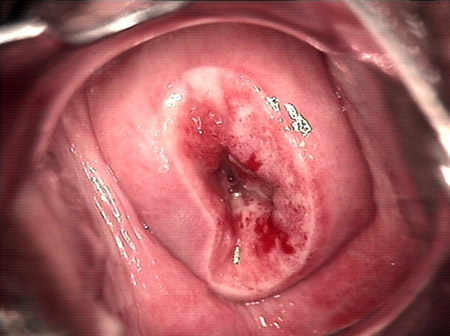

CIN 2-3

CIN 2-3 leep術(shù)后